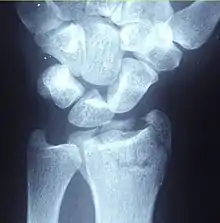

| A Colles fracture as seen on X-ray: It is a type of distal radius fracture. | |